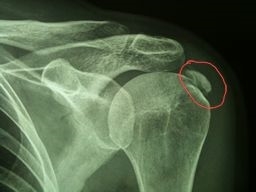

Ortopedski centar Ivanišević praktično jedini u bližoj okolici može odstraniti ovako velik kamen iz ramena artroskopskom metodom bez rezanja.